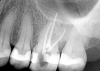

The patient returned for final evaluation of the provisional calcium-hydroxide endodontic therapy and resolution of the infection (33 days postoperatively). Fistula was not present; the tooth was not sensitive to percussion or mastication. The gold crown was removed using a high-speed metal cutting bur, the remaining caries were excavated conservatively, and the endodontic therapy was completed. Placement of glass-fiber reinforced composite and composite core buildup took place. The natural tooth structure to receive the glass-fiber post and a long-term restoration was available (Figure 8). Within one appointment, the tooth was restored (Figure 9). The patient was instructed to return for clinical and radiographic evaluation after 6 to 12 months to determine progression of periodontal healing. At that time, if the healing were adequate and the tooth were stable, evaluation of the tooth would be considered every 3 to 4 years.7

Fig 8. Gold crown removed, dentin excavated, canals shaped and filled.

Figure 8